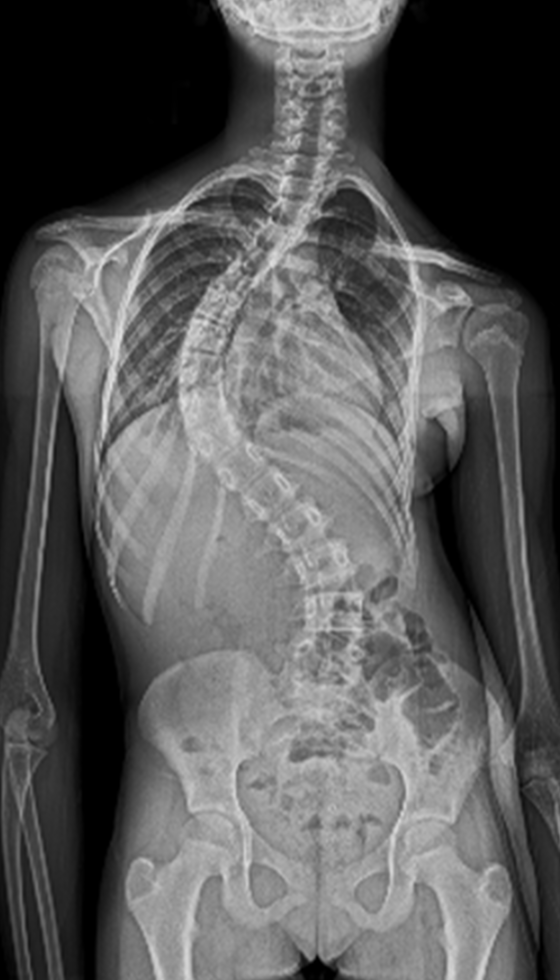

Gallery : Before - After